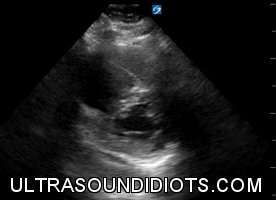

Examples of Normal

Examples of Parasternal View: